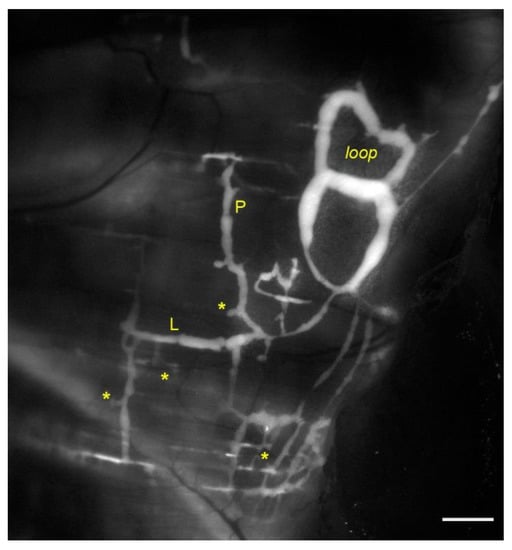

- Moriondo, A.; Solari, E.; Marcozzi, C.; Negrini, D. Spontaneous activity in peripheral diaphragmatic lymphatic loops. Am. J. Physiol. Heart Circ. Physiol. 2013, 305, H987–H995. [Google Scholar] [CrossRef]

- Negrini, D.; Marcozzi, C.; Solari, E.; Bossi, E.; Cinquetti, R.; Reguzzoni, M.; Moriondo, A. Hyperpolarization-activated cyclic nucleotide-gated channels in peripheral diaphragmatic lymphatics. Am. J. Physiol. Heart Circ. Physiol. 2016, 311, H892–H903. [Google Scholar] [CrossRef]